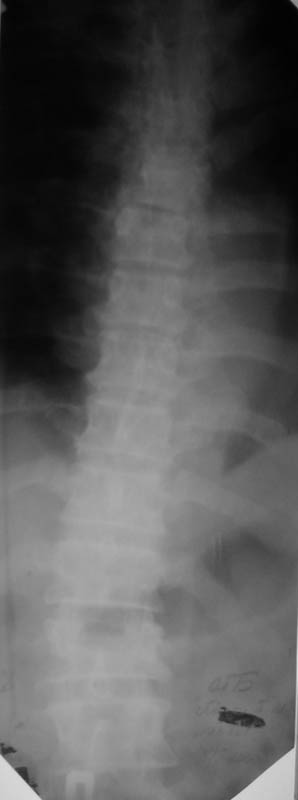

Мужчина, 48 лет. 8.04. 2000 г. - сочетанная травма: компрессионные переломы тел Th4- Тh6 и L1 позвонков с синдромом полного нарушения проводимости спинного мозга -

нижней параплегией, нарушением чувствительности и функции тазовых органов; переломы III-IV ребер справа,VI-VII ребер слева со смещением,травматический немопневмоторакс слева, гемоторакс справа, оскольчатые переломы обеих лопаток со смещением, перелом правой ключицы со смещением, тупая травма живота, ушиб сердца. Осложнения:посттравматическая пневмония, посттравматический плексит справа, цистит, пролежень в области крестца.

В настоящее время жалобы на отсутствие чувствительности в нижних конечностях, невозможность самостоятельной ходьбы (передвигается на кресле).КОНСУЛЬТАТИВНОЕ ЗАКЛЮЧЕНИЕ ЯМР-ТОМОГРАФИЧЕСКОГО ИССЛЕДОВАНИЯПроведена МР_томография грудного отдела позвоночника в сагиттальной проекции, с различной степенью контрастирования тканей, в режимах Т1 и Т2 В/И + МР-миелоурография. Визуализированы: спинной мозг с уровня D1 до уровня D12, тела позвонков D1-D12, межпозвонковые диски. Спинной мозг на уровне D4-D6 истончен с неровными нечеткими контурами, гетерогенной структуры, умеренно пониженной интенсивности на Т1 В/И, без очаговых изменений. Отмечается клиновидная деформация тела D5, снижена высота тела D4, структура его гетерогенная. Обращают внимание выраженные дегенеративные изменения дисков в грудном отделе позвоночника: снижение их высоты, изменение структуры изображения за счет исчезновения высокоинтенсивного сигнала от ядер. При исследовании в режиме МР-миелоурографии ликворный сигнал на уровне D4-D5 почти прерывается, интенсивность его существенно снижена.

ЗАКЛЮЧЕНИЕ: ПОСЛЕДСТВИЯ КОМПРЕССИОННОГО ПЕРЕЛОМА ТЕЛА D4-D5 С КОМПРЕССИЕЙ СПИННОГО МОЗГА. МРТ-ПРИЗНАКИ МИЕЛОПАТИИ И РУБЦОВО-СПАЕЧНОГО ПРОЦЕССА В ПОЗВОНОЧНОМ КАНАЛЕ НА УРОВНЕ D4-D5. ВЫРАЖЕННЫЕ ДЕГЕРАТИВНЫЕ ИЗМЕНЕНИЯ ДИСКОВ В ГРУДНОМ ОТДЕЛЕ ПОЗВОНОЧНИКА.